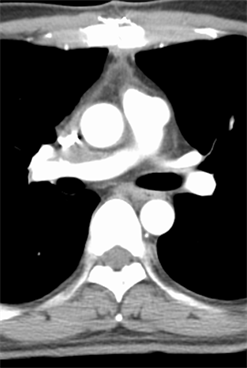

A 47-year-old man was referred to our institute with an enlarging left RCC. Computed tomography scanning revealed a large enhanced mass in the left kidney (Figure 1(a)) and local extension into the infrahepatic IVC (Figure 2) with pulmonary tumor embolism (Figure 3(a)). The embolism was located at the proximal portion of the right pulmonary artery, with no suspicious lesions in the left lung. As the mass of the RCC had been rapidly increasing in size for the past 2 months, early surgery was scheduled.

After sufficient anticoagulant treatment, the patient was discharged without any complications (Figure 1(b), Figure 3(b)). He is currently doing well with no evidence of recurrent disease or other metastases at a follow-up of 10 months. Follow up computed tomography revealed no recurrences and other metastases.

Figure 3. (a) Preoperative computed tomography scan showing tumor embolism in the right pulmonary artery (white arrow head); (b) Postoperative computed tomography scan showing no pulmonary tumor emboli.